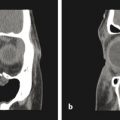

Another similar radiographic presentation to a traumatic bone cyst is the aneurysmal bone cyst (ABC). This lesion tends to favor the female population, and often, there can be jaw swelling and pain. The most common type is the vascular type, which can be rapid growing and destructive (Fig. 9‑4a, b). Unlike a traumatic bone cyst, on entry of this lesion, you will encounter brisk bleeding, which is controllable with pressure and resolves with curettage of the lesion (Fig. 9‑4c–e). Aneurysmal bone cysts tend to have a recurrence rate of 10% and are part of a spectrum of vascular lesions; these cysts are associated with jaw tumors.